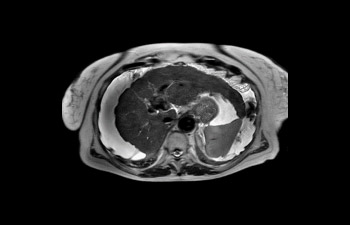

Find the right clinical applications for your needs